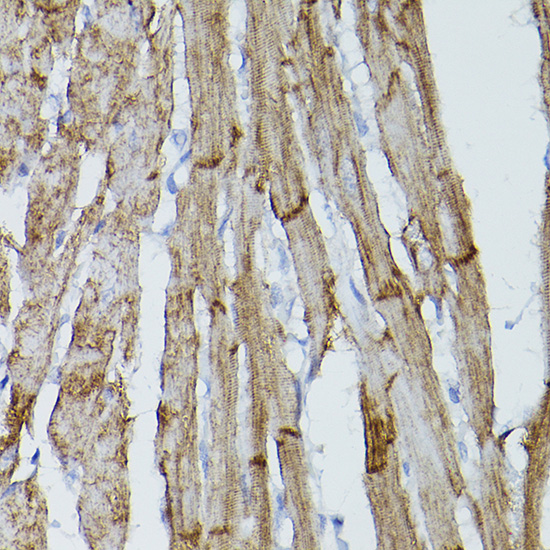

Immunohistochemistry of paraffin-embedded mouse heart using PDGFRA Rabbit pAb.